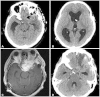

lnflammatory pseudotumor (IPT) is a rare, non-neoplastic inflammatory process. It is most commonly occurs in the orbit, but extension into brain parenchyma is uncommon. In a confirmed case of IPT, most cases show good improvement with steroid theraphy. A 50-year-old man with progressive left-eye visual disturbance and mass lesion was admitted in a hospital. A left orbital mass biopsy revealed what was highly suspected as an inflammatory pseudotumor. Steroid pulse therapy with dexamethasone, radiation therapy, and chemotherapy with amphotericin B were performed, but they were not effective in improving the condition of the patient. Revision open surgery was then performed. A follow-up brain enhancement computerized tomography showed an enlarged mass volume and hydrocephalus with periventricular enhancement. As an additional procedure, ventriculoperitoneal shunt and tuberculosis medication were administered. About 2 weeks later, clinical symptoms and radiologic findings improved. We present a case of intra-cranial IPT and discuss further treatment methods.